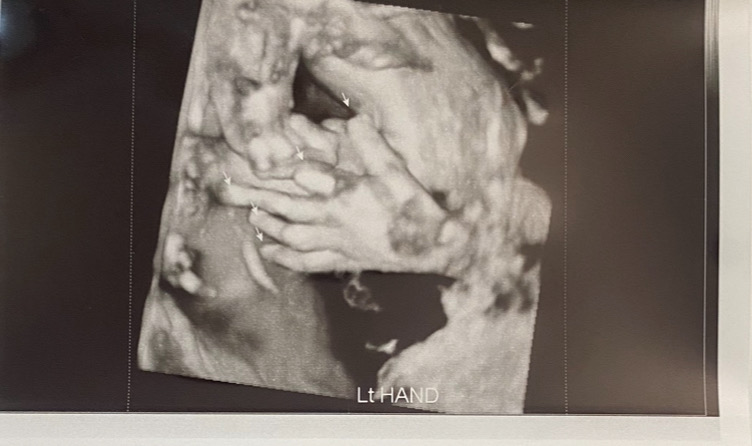

입체춈파 아기 얼굴 보기 힘드네여😅

임신 25주차이고 임당 검사 겸 입체춈파 보는데 아기가 고개를 푹 숙이고 있어서 얼굴을 못보고 나왔어요 ㅋㅋ ㅠ 아침에 공복 상태로 검사했는디 애기가 배고파서 그런 걸까요? 그 와중에 손가락은 선명하게 잘 나왔네여ㅎㅎ 담주 목욜에 다시 입체 춈파만 예약했는데 든든하게 잘 먹고 단 음료도 먹고 가서 애기 얼굴 보려구요 👼

와! 아기들 손은 다 도라에몽 같을 줄 알았는데 섬섬옥수네요!!ㅎㅎ

그니까용 ㅎㅎ 아가 손이 저렇게 늘씬할 줄 몰랐네여 👼

손가락이. 길죽길죽하니 넘 이뻐요!

감사합니다 ㅎㅎ 손가락 예쁜 건 남편 손 닮은 것 같아여 🤭